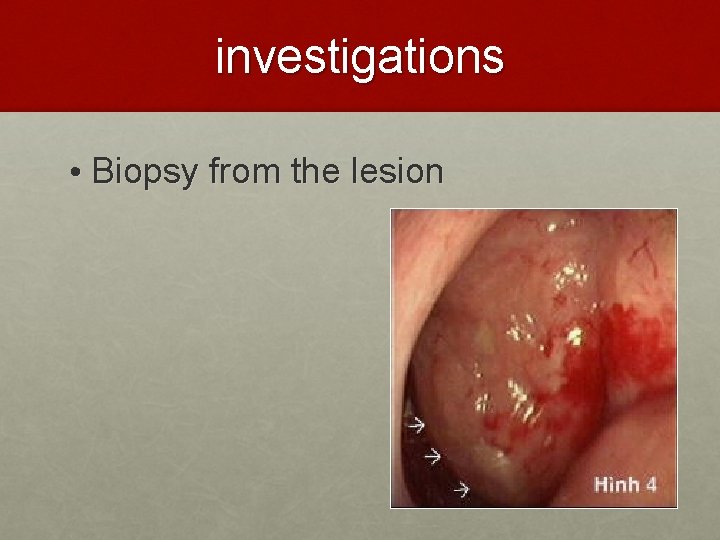

investigations • Biopsy from the lesion